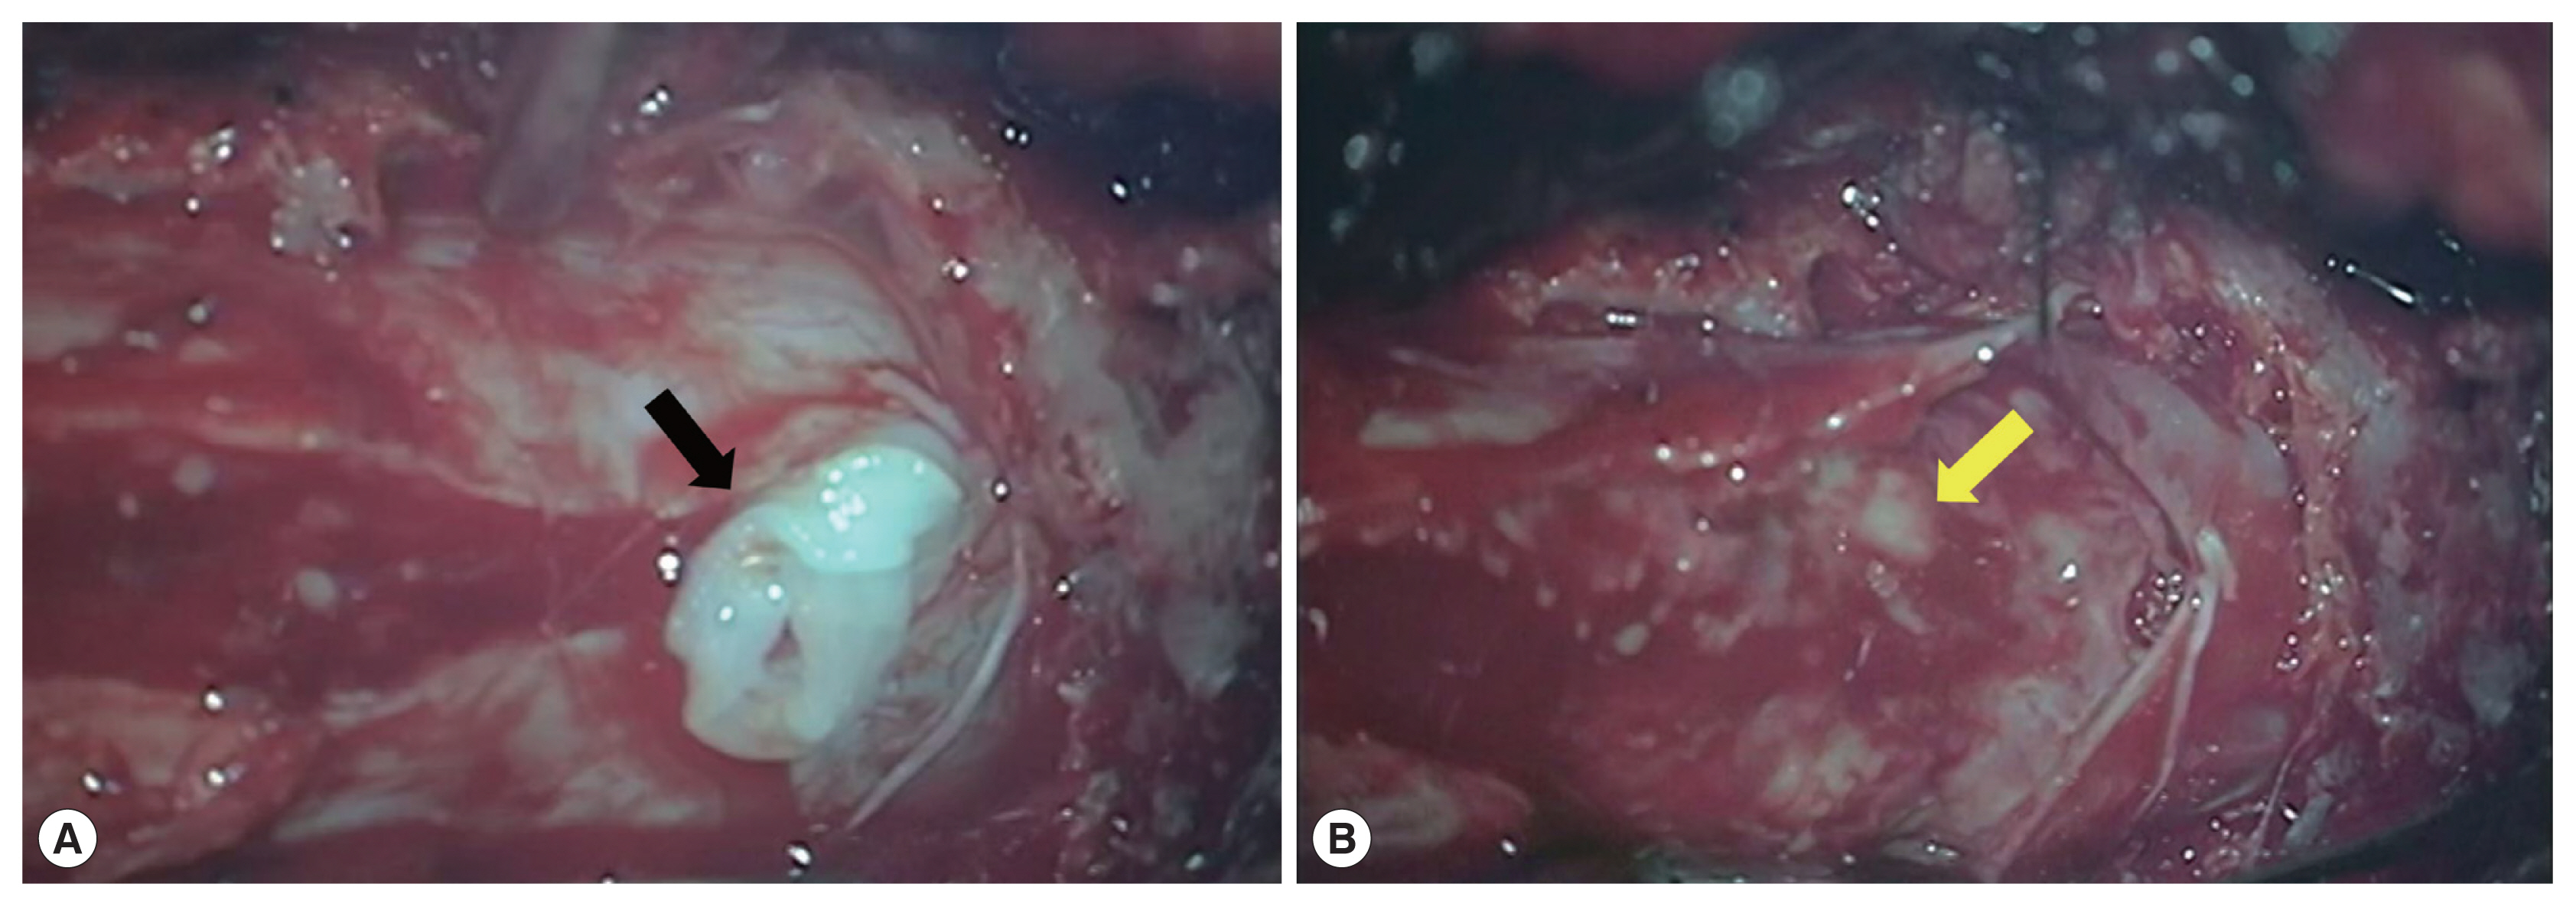

A 56-year-old man presented with a 1-week history of perianal pain. No history of dysuria or difficulties in defecation were reported. And the muscle strength of the bi-upper and bi-lower limbs was grade 5 in the MRC scale. The muscle tonus of the 4 limbs was normal, with normal tendon reflexes in the upper and lower limbs. And laboratory assessment revealed that white blood cell count of 6,200/μl (reference range 4,000–10,000/μl ), with 1.9% eosinophil count (reference range 0.4–8.0%). Further examinations such as blood biochemistry, routine stool examination, and urine analysis were within normal range. MRI of the lumbosacral spine with gadolinium contrast study showed a 1.7×1.5×5.4 cm heterogeneous enhancing mass at the S1–2 level (Fig. 1). We initially considered the possibility of a neoplastic lesion. The patient underwent laminectomy from S1 to S2. On the operative view, we found that the dural tension was very high, the arachnoid membrane was thickened and yellowish-white due to severe inflammation and adhesion. We detected a live worm in inferior margin of L5 (Fig. 2A), proliferative inflammatory granulation tissue (Fig. 2B) surrounding the nerve tissue of cauda equina, which is not easy to remove. We did not remove inflammatory granulation tissue, just only took the worm body out from it.